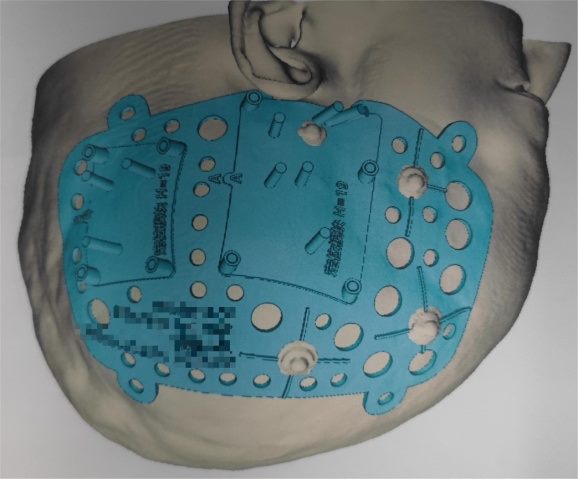

放射性粒子植入属于组织间植入近距离治疗范畴,是放射治疗的方法之一,主要通过影像引导技术(CT、彩超、磁共振)通过介入穿刺针,像子弹一样将密封的放射源直接打入肿瘤病灶内,通过放射性核素持续释放射线对肿瘤细胞进行杀伤的一种治疗手段。放射性碘-125粒子能以27-35kev能量放射出γ射线,半衰期为60.2d。γ射线有效辐射半径10-15mm内肿瘤细胞的DNA,干扰肿瘤细胞DNA合成,诱导细胞凋亡,杀灭肿瘤细胞,小血管,小神经等,达到缩小肿块,缓解疼痛的目的。放射性粒子在治疗实体肿瘤具有精度高、创伤小和疗效肯定等优势,近年来3D打印模版技术的发展进一步提高了精度、安全性,缩短了手术时间。

碘-125放射性粒子3D打印模版在颅脑肿瘤碘-125植入术